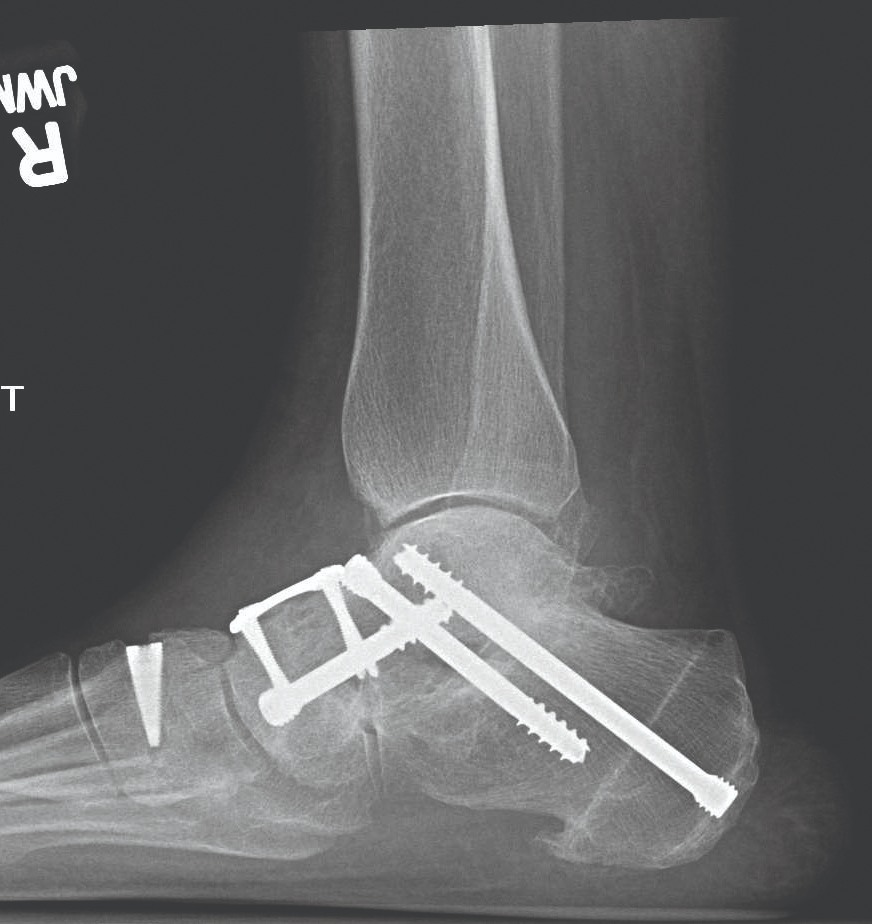

Stopa została zrekonstruowana przy użyciu metalowych śrub i prętów, ale z powodu błędów i opóźnień w systemie medycznym musiałam czekać aż 19 miesięcy na operację, żyjąc przez ten czas w ciągłym bólu i ograniczeniu ruchu.

Moja noga jest wypełniona metalem, a całe ciało musi nauczyć się stabilności i bezpiecznego poruszania się od nowa. Każda wpłata i każde udostępnienie tej zbiórki to dla mnie realna szansa na samodzielność, bezpieczeństwo i odzyskanie sprawności.

My health problems began in 2018 when I was involved in a serious car accident. Since then, I have been fighting to regain my health and mobility. Unfortunately, fate was not kind to me again in 2024, I suffered another very serious accident, in which I broke my right ankle in multiple places.

My foot was reconstructed using metal screws and rods, but due to errors and delays in the medical system, I had to wait 19 months for surgery, living all that time in constant pain and limited mobility.